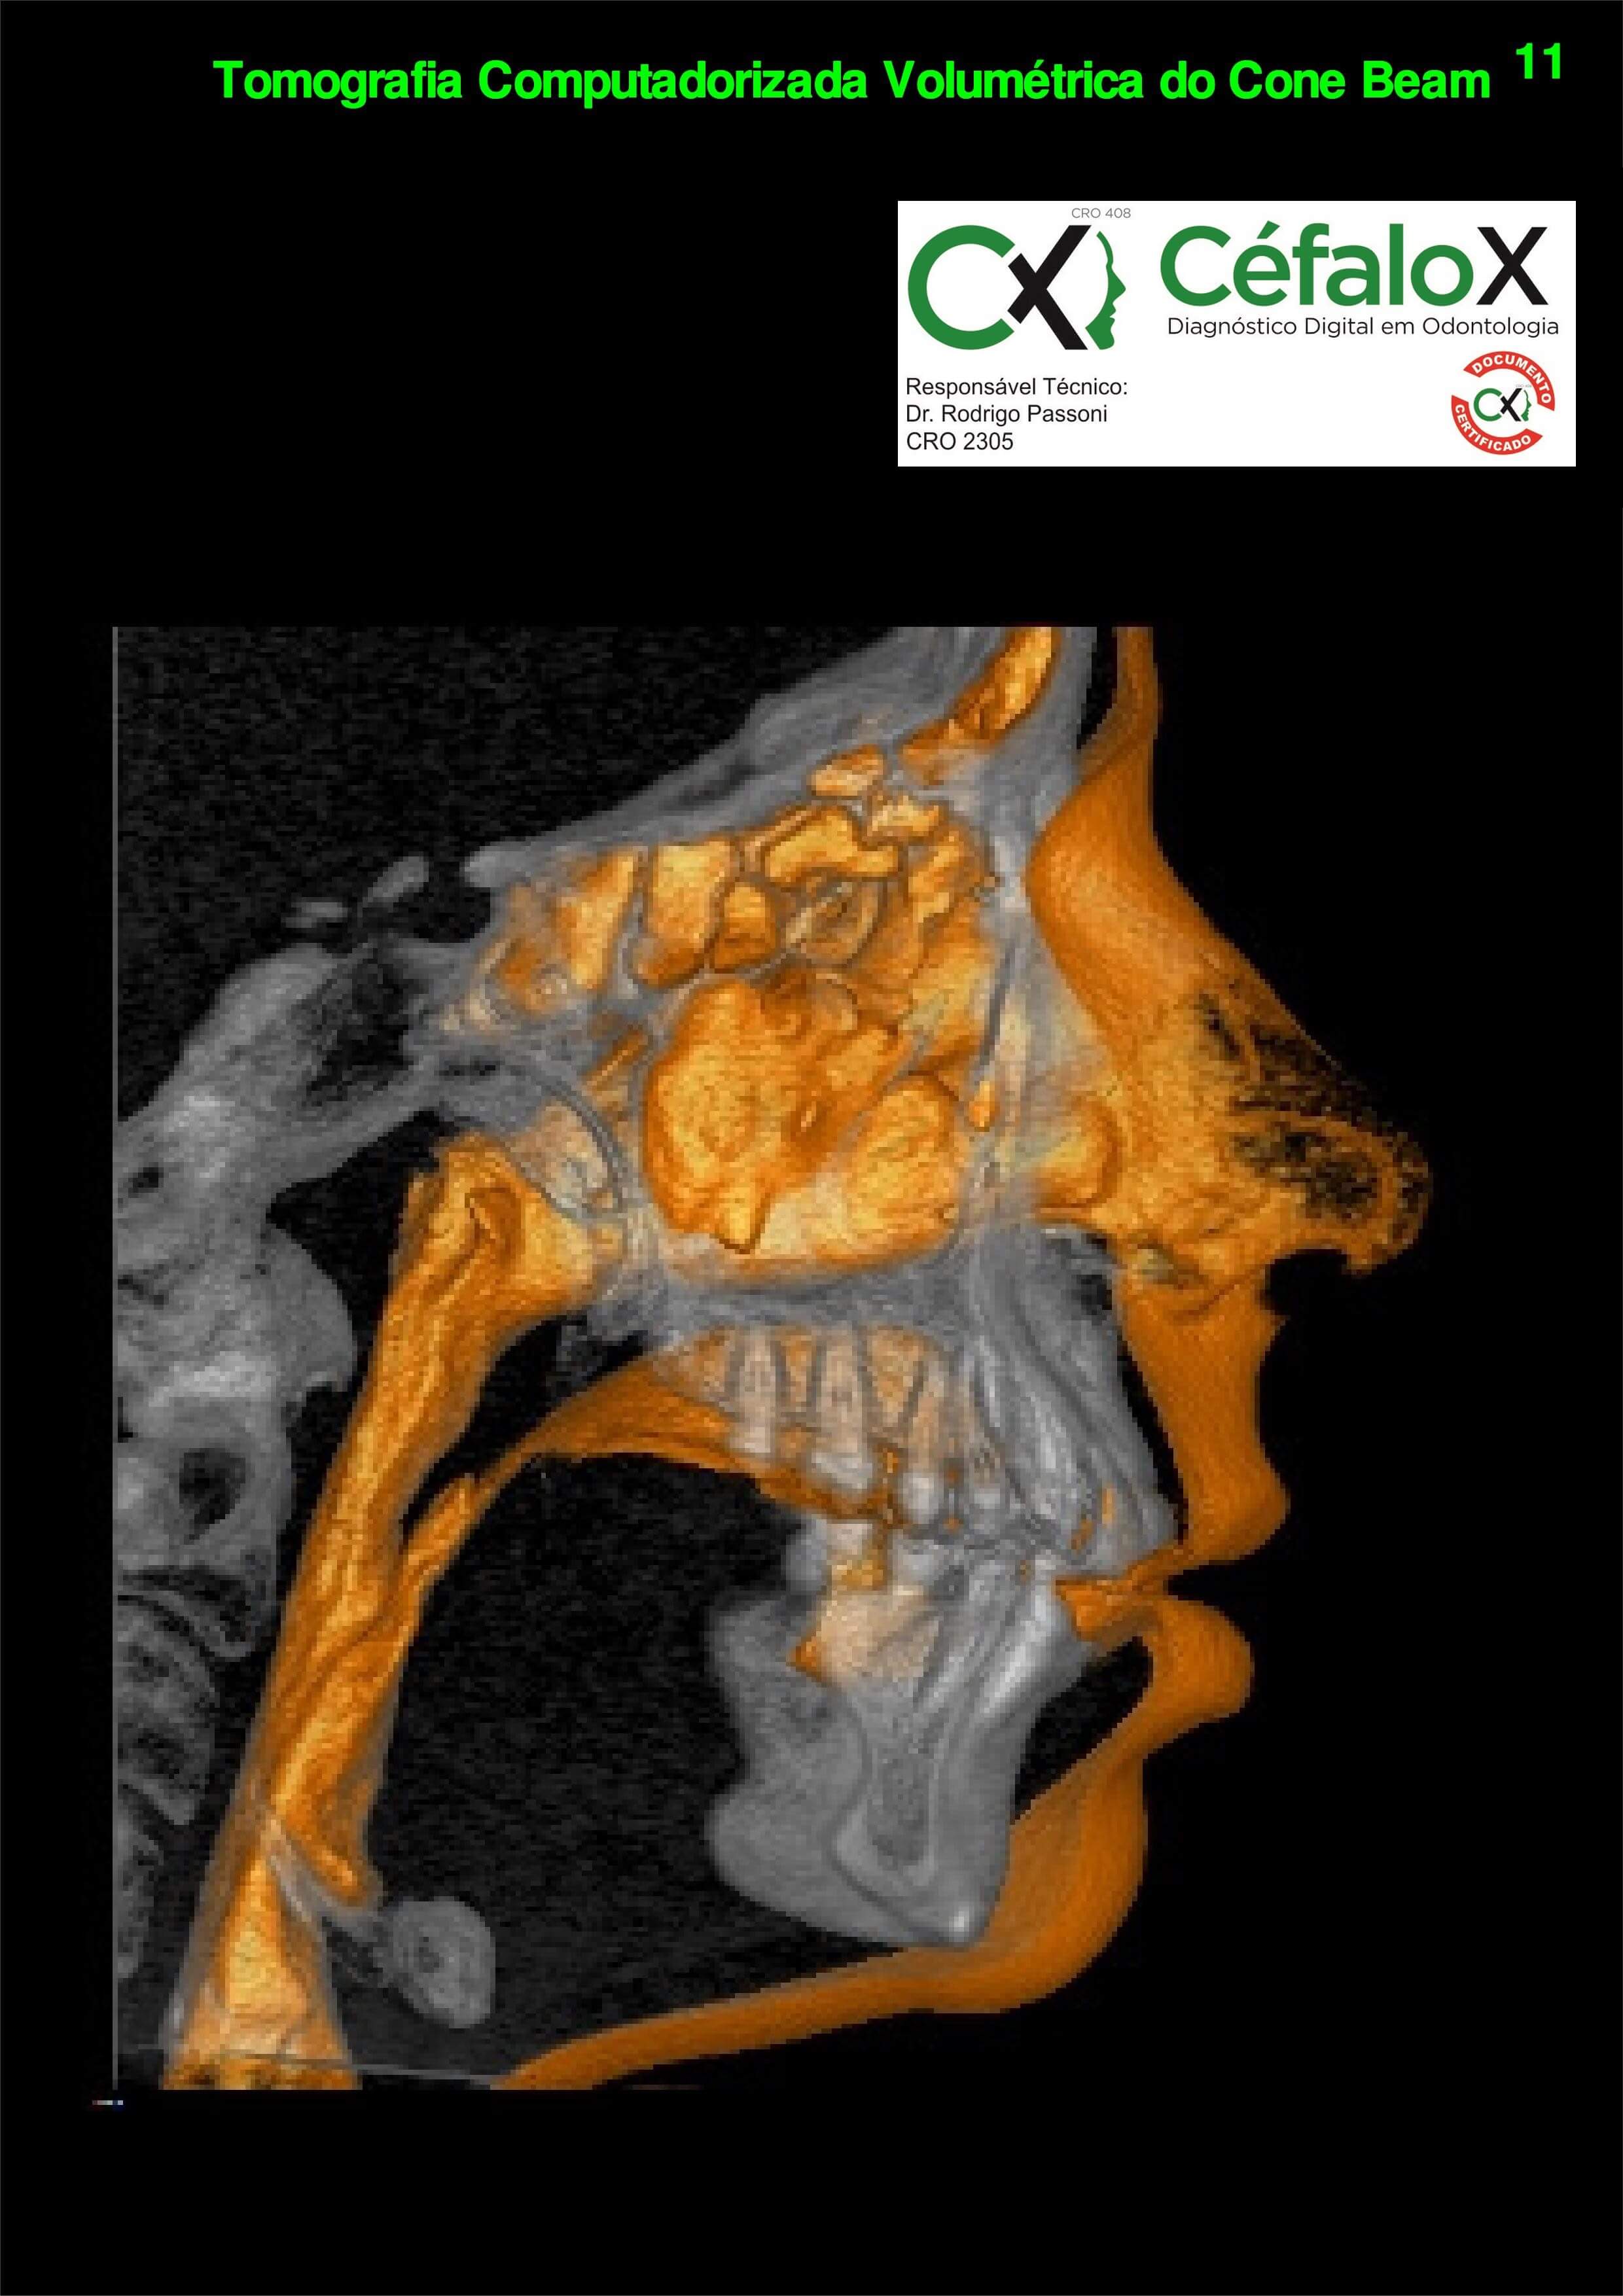

TC de face (do Hióide à Glabela), reconstrução 3D do tecido ósseo, radiografia panorâmica, telerradiografia lateral com traçado, cortes transversais e axial de maxila e mandíbula e arquivo DICOM- entregue em pasta de Pvc.

TC de face (do Hióide à Glabela), reconstrução 3D do tecido ósseo, radiografia panorâmica, telerradiografia lateral e frontal com traçado, cortes transversais e axial de maxila/mandíbula e arquivo DICOM – entregue em pasta de Pvc.

TC de face (do Hióide à Glabela), reconstruções 3D do tecido mole/ósseo/vias aéreas, radiografia panorâmica, telerradiografia lateral e frontal com traçado, cortes transversais e axial de maxila/mandíbula, ATM e arquivo DICOM – entregue em pasta e caixa de Pvc.